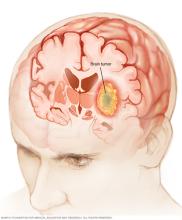

A brain tumor can form in the brain cells (as shown), or it can begin elsewhere and spread to the brain. As the tumor grows, it creates pressure on and changes the function of surrounding brain tissue, which causes signs and symptoms such as headaches, nausea and balance problems.

A brain tumor is a growth of cells in the brain or near it. Brain tumors can happen in or near the brain tissue. Nearby areas where brain tumors can happen include nerves, the pituitary gland, the pineal gland and the membranes that cover the surface of the brain.

Brain tumors can begin in the brain. These are called primary brain tumors. Sometimes, cancer spreads to the brain from other parts of the body. These tumors are secondary brain tumors, also called metastatic brain tumors.

There are many different types of primary brain tumors. Some brain tumors are not cancer. These are called noncancerous brain tumors or benign brain tumors. Noncancerous brain tumors may grow over time and press on the brain tissue. Other brain tumors are brain cancers, also called malignant brain tumors. Brain cancers may grow quickly. The cancer cells can invade and destroy brain tissue.

Brain tumors happen when there are changes in the DNA of the cells in or near the brain. A cell's DNA holds the instructions that tell the cell what to do. The changes tell the cells to grow quickly and continue living when healthy cells would die as part of their natural life cycle. This makes a lot of extra cells in the brain. The cells can form a growth called a tumor. The tumor can grow to invade and destroy healthy tissue.